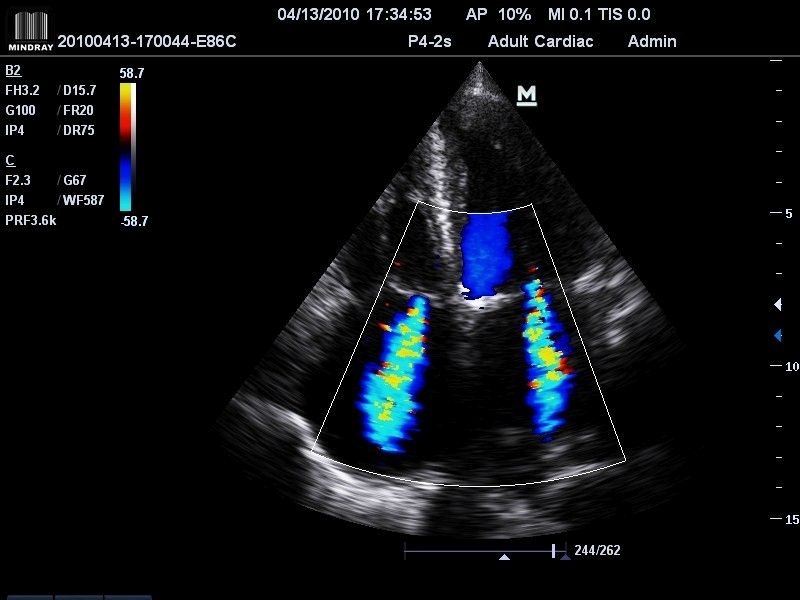

Klinické obrázky:

- High Sensitivity Flow

- 2 živé obrazy B/CFM (Dual live B/CFM mód)

- triplexný mód a automatické pomeranie celého spektra Pulzného Dopplera

- Pulzný, Spektrálny Doppler (PW), citlivý Farebný Doppler (CFM), ultracitlivý smerový Power Doppler (PDI), anatomický - M mód a Stress Echo